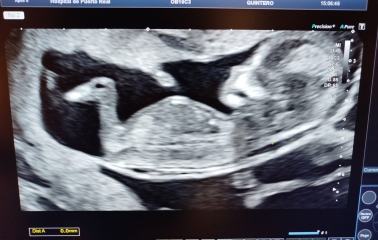

Hi all! Sorry I´ve been away from mumsnet for a while. I´ve been really busy lately and also everytime I thought about reading the thread I couldn´t shake the feeling that I was making everything up. Sometimes I can´t believe it´s happening buuuuut....

I had another scan today and saw the babies and for today it all seems real again 😂I will post the pictures (hope the site allows me to do it).

They all are in different sacs with individual placentas. All seems well.

OMG! It's triplets!!!